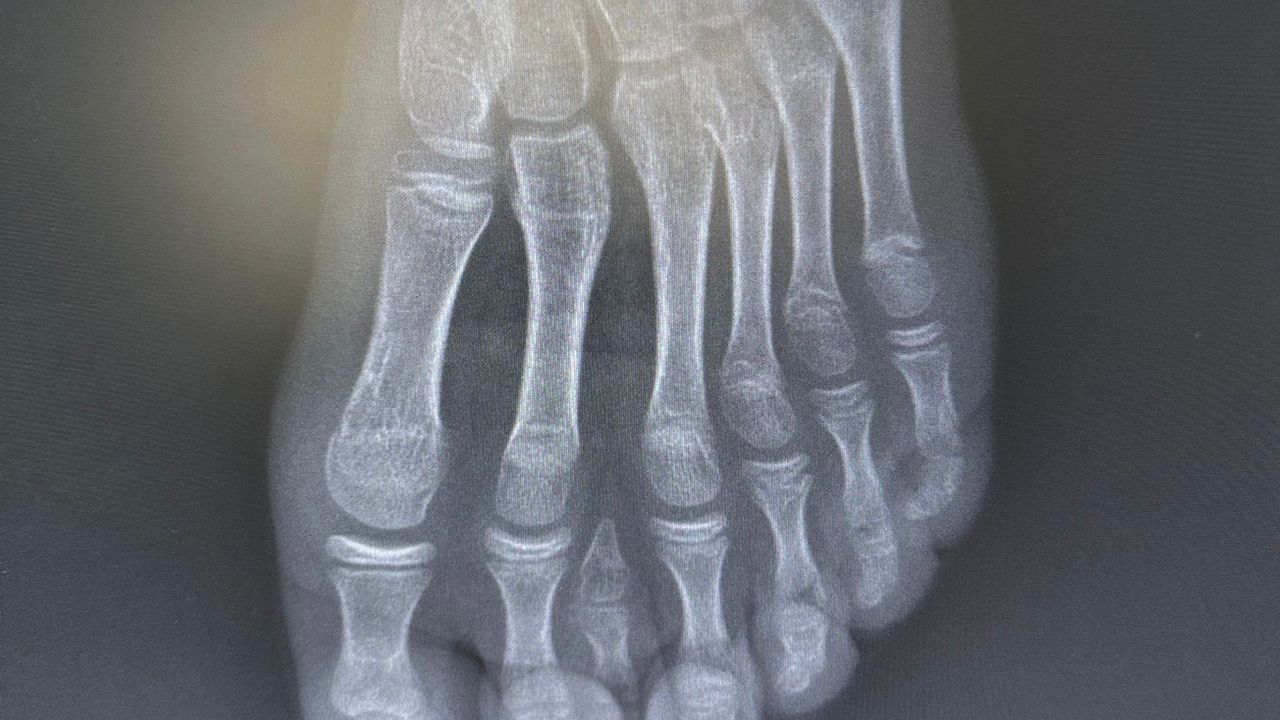

Genel yaklaşımda bu tür vakalarda cerrahi planlamanın ayağın beş parmaklı anatomik yapısına uygun şekilde yapıldığı ifade edildi. Ancak hastanın yapılan detaylı klinik ve radyolojik değerlendirmelerinde altı parmağın; falanks (parmak kemikleri), metatars (tarak kemikleri) ve diğer ayak kemikleri ile uyumlu ve düzgün şekilde geliştiği tespit edildi.

Uzmanlar, mevcut altı parmağa müdahale edilmesinin ayak biyomekaniğini ve dengesini olumsuz etkileyebileceğini değerlendirdi.

Bu doğrultuda cerrahi planlama yeniden yapılarak, fonksiyonel açıdan yetersiz ve estetik olarak problem oluşturan tek parmağın çıkarılmasına karar verildi. Operasyon sırasında diğer parmaklara ait damar ve sinir yapıları titizlikle korunurken, mikrocerrahi teknikler kullanılarak işlem sorunsuz şekilde tamamlandı.